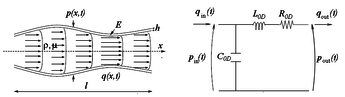

Boundary conditions from multiscale modeling of circulation: Another approach to impose the boundary conditions is to use reduced models, as 1D model or 0D (lumped) models. 1D and 0D models are mathematical models able to reproduce the systemic and pulmonary circulation. Figure 10 shows a standard approach to provide realistic local boundary conditions for 3D CFD simulations at the specific arterial domain using 1D models of the entire arterial tree and 0D models at the distal ends[83]. 1D model solves the Navier-Stokes equations under some assumptions (see appendix 9) and lumped models (0D models) can be derived from electrical circuit analogies where blood flow is represented by the current and arterial pressure by the voltage. Usually the electrical components of these circuits are resistances, inductances and capacitors. Where resistances represent arterial and peripheral resistance that occur as a result of viscous dissipation inside the vessels, capacitors represent volume compliance of the vessels that allows them to store large amounts of blood, and inductors represent inertia of the blood[75]. The values of these electrical components can be estimated from physical data of the subject [84][85]. This approach is quite used because it is capable to account for the effect of local pathological conditions on the whole circulatory system, providing realistic boundary conditions for the 3D problem [75][79][86].